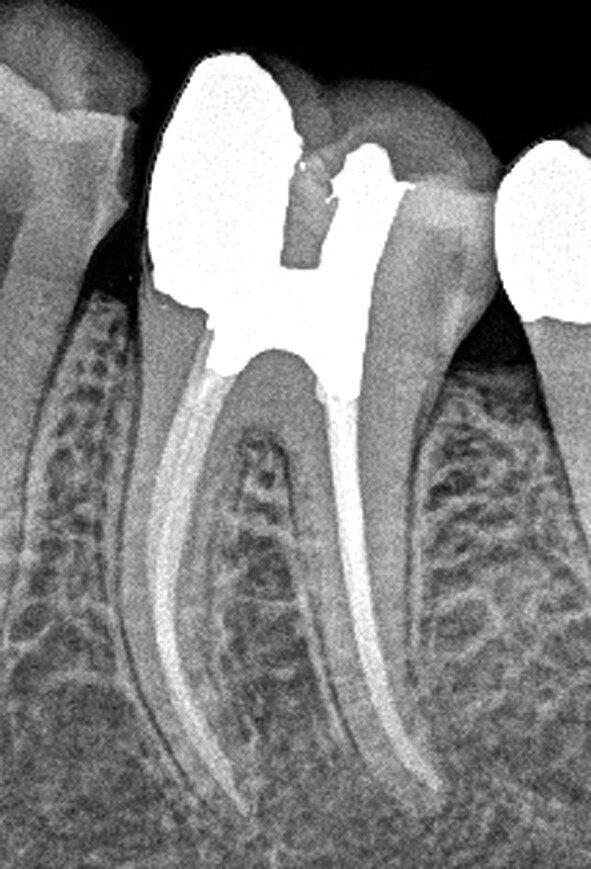

Figs. 4a et b : Cavités d’accès réalisées dans une molaire préparée pour une couronne et requérant un traitement canalaire (à gauche). Radiographie postopératoire (à droite) montrant le résultat admirable de la mise en forme du canal radiculaire, du nettoyage et de l’obturation – malgré la dimension minimale de l’orifice d’accès. À noter le plafond de la cavité pulpaire qui subsiste largement. (Photos : fournies par le Dr Steve Baerg)